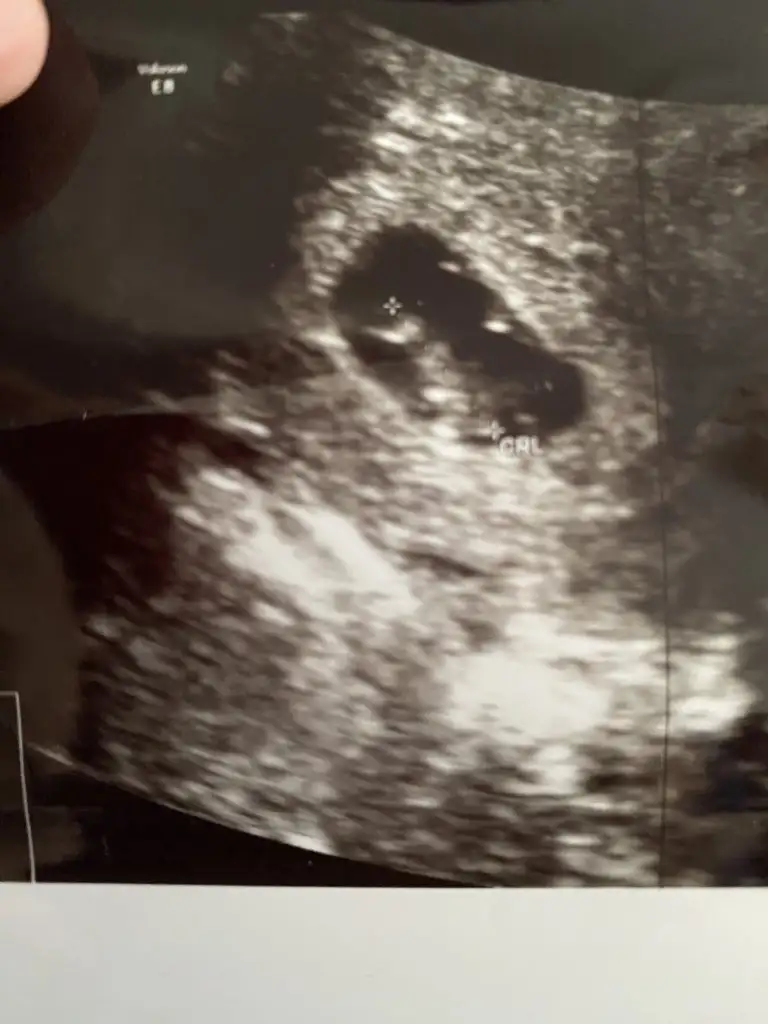

Benimde çin takvimine göre erkek çıkıyoduCanım şöyle 5-6 haftalık ultrason resmin varsa yüklermisin şu ramzi teorisi doğru mu ona bakıcam

Bu ultrason vajinal bakıldıysa ramzi teorisi çürür karından bakıldıysa ramzi teorisi doğru demektir ama Çin takvimi tutmuş bizde de tutarmı acabaBenimde çin takvimine göre erkek çıkıyodu

benimde fasulye gibi kız mı çıkar dersinHeH bak o teori yalan çünkü görümcemin fasülye gibi ilk ultrason resmî. Ve bebek kız

Karından bakıldı canımBu ultrason vajinal bakıldıysa ramzi teorisi çürür karından bakıldıysa ramzi teorisi doğru demektir ama Çin takvimi tutmuş bizde de tutarmı acaba

Benim kesede hep fasulye gibiydiBide ilk ultrasonlarda kesenin şekli yuvarlaksa kız fasulye gibiyse erkek diyorlardı yavalla benim teoriler karmakarışık çıktığından hangisine uyarsa modundayım ama sende hepsi erkek diyor kız çıkarsa bu teorilere olan inancım sarsılacak hadi hayırlısı cuma ola hayır ola belki tahminde bulunur doktorlar

Benim yuvarlak bak tek burda kız çıktı eğe kızı. Olursa birtek bu tutmuş olur ama görümcemin ki fasülye gibi. Eltiminki yuvarlak ikisinin de kızı olduCuma 13:30 randevum sen benden önce öğrencen tahminde bulunursaCuma sorcam söylemezse ptesi devlette bidaha sorcam rasgele boşlukta olan bi doktora randevu aldım hiç bilmiyorum iyimi kötümü umarım iyi bi doktorla karşılaşırım

benimde fasulye gibi kız mı çıkar dersin

Ozaman benim o teoriye göre kızKarından bakıldı canım

bu teoriye göre erkekBenim kesede hep fasulye gibiydi